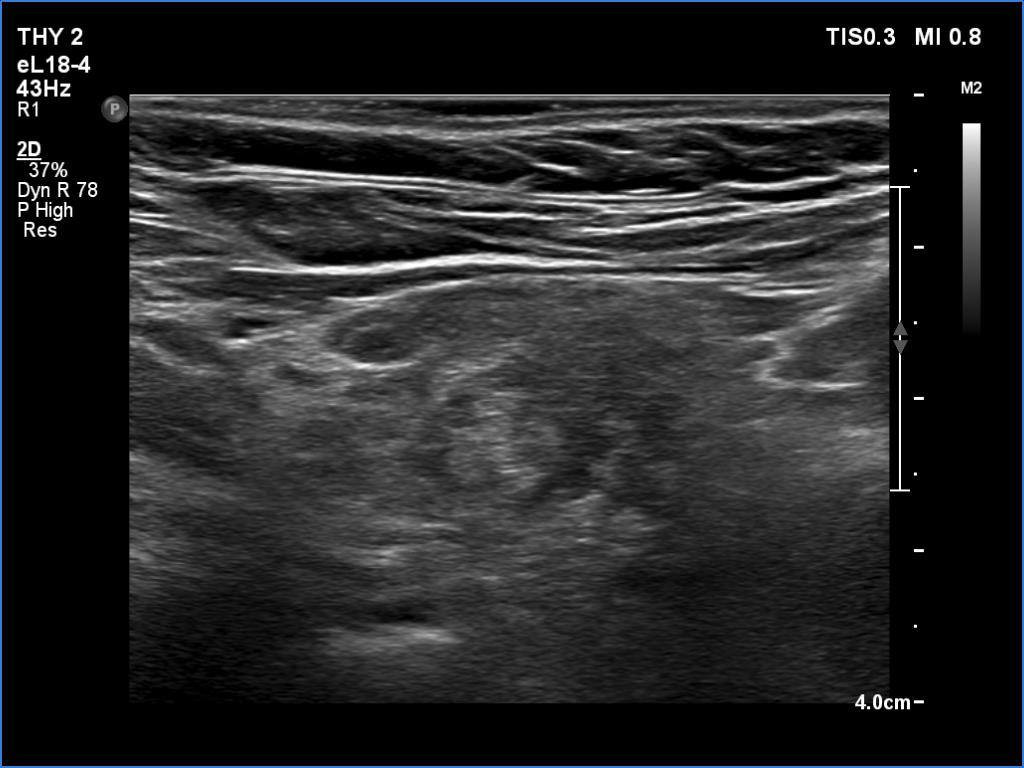

Ultrasonography: The right lobe had several discrete hypoechoic areas within an echonormal background. The left lobe had a larger hypoechoic area resembling the presentation of central hypoechoic area-type form.

Comment: The central hypoechoic area-type presentation is always bilateral. The pattern in this case should be regarded as focal form of lymphocytic thyroiditis.